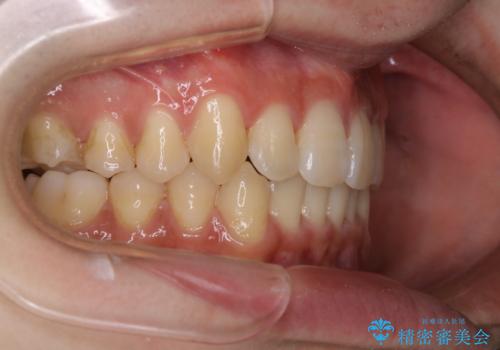

インビザライン:前歯のがたつきと噛み合わせの治療

- 前歯のがたつきが気になるとご相談にいらした方です。左の奥歯の噛み合わせのズレも認められたため、インビザライン治療にて改善しました。

主訴である前歯のガタつきだけでなく、奥歯の噛み合わせからしっかり治療したため、治療期間が長めとなりました。患者様ご本人としては治療の途中で一時的にモチベーションが下がったこともあったようですが、最後まで頑張って続けて頂けたことで噛み合わせ及び見た目の改善を行うことが出来ました。